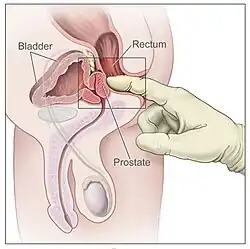

Men suspected of having prostate cancer may undergo several tests to assess the prostate. One common procedure is the digital rectal examination, in which a doctor inserts a lubricated finger into the rectum to feel the nearby prostate.[23][24] Tumors feel like stiff, irregularly shaped lumps against the rest of the prostate. Hardening of the prostate can also be due to benign prostatic hyperplasia; around 20–25% of those with abnormal findings on their rectal exams have prostate cancer.[25] Several urological societies' guidelines recommend magnetic resonance imaging (MRI) to evaluate the prostate for potential tumors in men with high PSA levels. MRI results can help distinguish those who have potentially dangerous tumors from those who do not.[26]